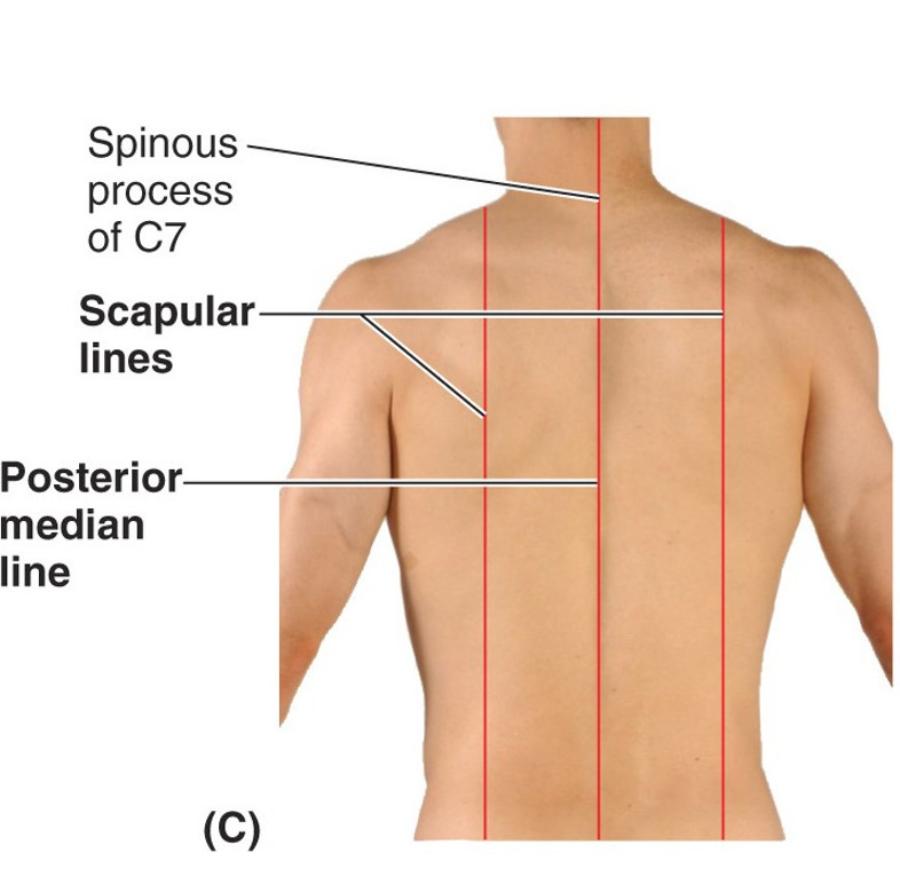

how to count vertebrae, whats the easiest to do?

find C7 which is the biggest bump and then count down in that direction

look at picture

Identify 2 bony landmarks of the posterior thorax

- What is “CVA tenderness”?

Spinous processes of thoracic vertebrae 1 -12

Costovertebral angle (CVA)

- Clinical: “CVA tenderness”: a medical test in which pain is elicited by percussion of the area of the back overlying the kidney...The test is positive in people with an infection around the kidney

name the 2 posterior vertical lines and describe them?

another 2 names for the 1st one?

Posterior median (midspinal or midvertebral) line ...vertical line through spinous processes of vertebrae in mid-saggital plane

Scapular lines...vertical lines that pass through inferior angles of the scapula, line is parallel to posterior median line

posterior median line goes through the inferior angle of the scapula...look for it in the picture and try to picture the bottom of the scapula along the line